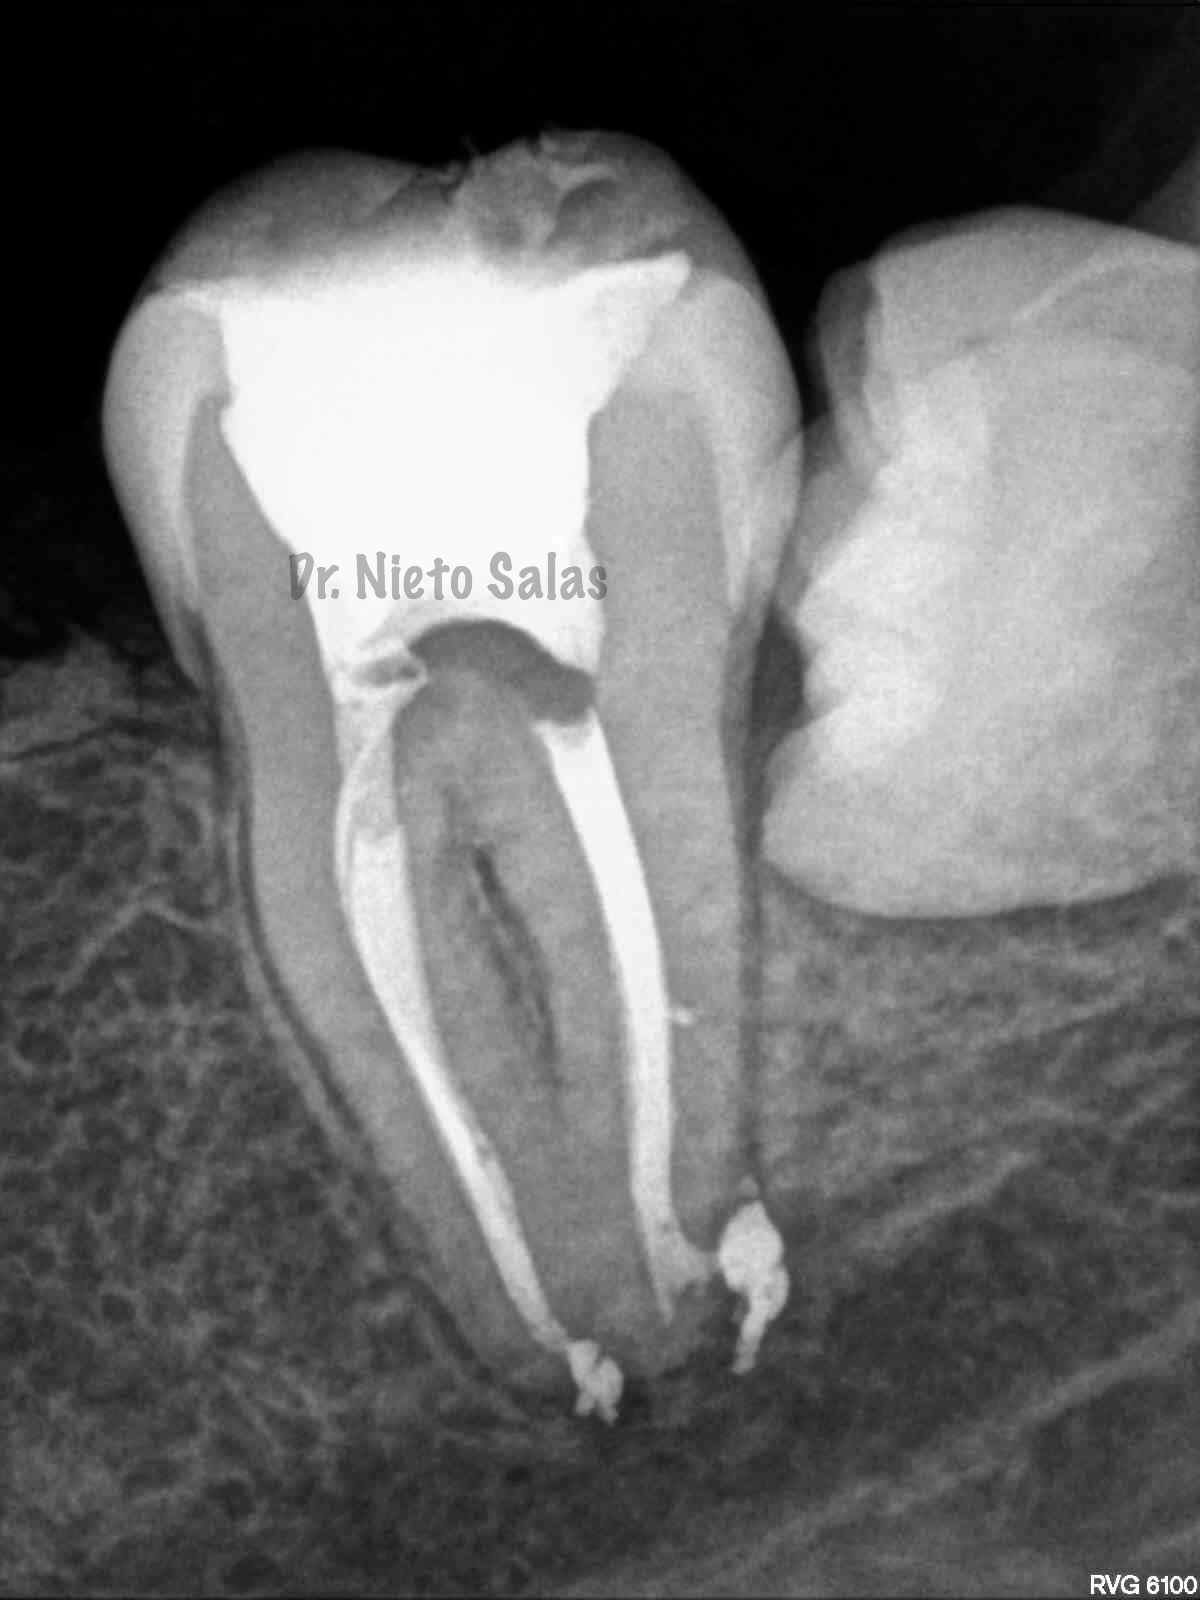

Así pues quedaría el sellado hermético y tridimensional:

2. disculpe, en las imagenes de la entrada de los conductos, era dos conductos distales o era solo uno ?? muchas gracias y enhorabuena por el casa, es perfecto !!

3. Dr Nieto Salas, en la imagen en que se ven la camara con la entrada de los conductos y la gutapercha, el orificio de entrada en distal era muy ancho, a parte de conductos laterales, localizo un conducto o dos conductos ?? ( la duda es por lo ancho de la entrada). El caso es maravilloso. Le doy mi enhorabuena.

4. Hola Juan,

en ese caso en particular, el número de conductos era solamente uno, ya sabes que los conducto distales en muchas ocasiones tienen forma ovalada, con lo que la entrada puede corresponder con las imágenes.